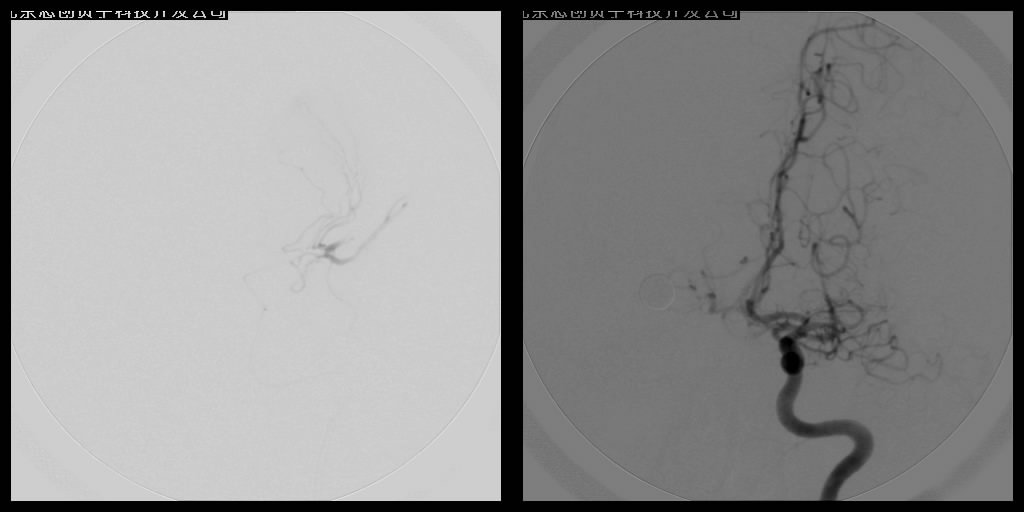

脑血管内介入栓塞术

血管栓塞术主要应用于出血性脑血管病的介入治疗,如对颅内动静脉畸形的栓塞、硬脑膜动静脉瘘栓塞、颈内动脉海绵窦瘘的栓塞、头颈部高血运肿瘤的栓塞等。

血管内溶栓及机械取栓